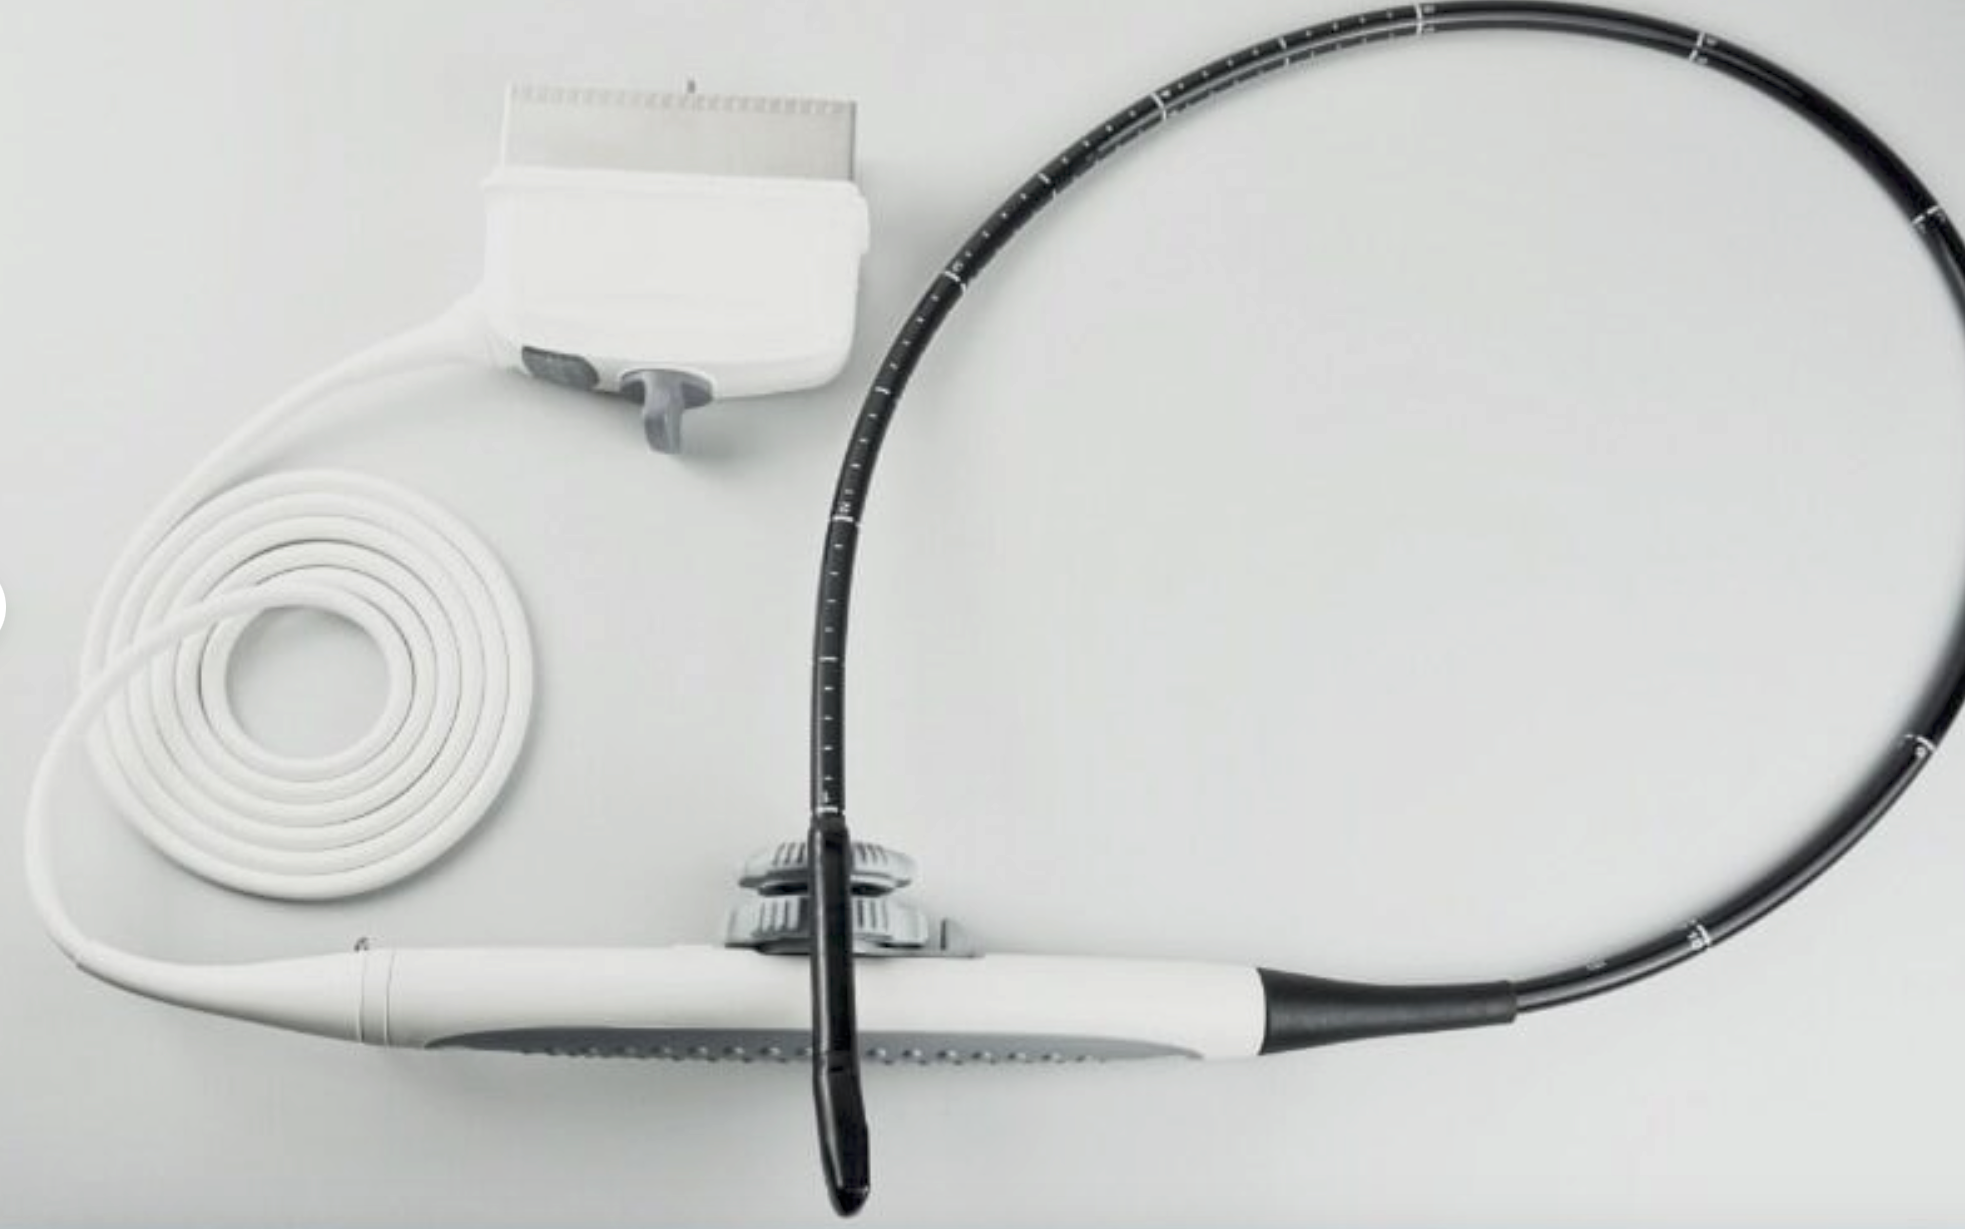

Philips C8-4V Curved Array IVT Ultrasound Probe

Sale price$ 1,226.72